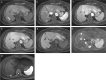

Gadolinium ethoxybenzyl diethylenetriamine pentaacetic acid (Gd-EOB-DTPA; Gadoxetic acid; Gadoxetate disodium) is a hepatocyte-specific MR contrast agent. It acts as an extracellular contrast agent in the early phase after intravenous injection, and then is taken up by hepatocytes later. Using this contrast agent, we can evaluate the hemodynamics of the liver and liver tumors, and can therefore improve the detection and characterization of hepatocellular carcinoma (HCC). Gd-EOB-DTPA helps in the more accurate detection of hypervascular HCC than by other agents. In addition, Gd-EOB-DTPA can detect hypovascular HCC, which is an early stage of the multi-stage carcinogenesis, with a low signal in the hepatobiliary phase. In addition to tumor detection and characterization, Gd-EOB-DTPA contrast-enhanced MR imaging can be applied for liver function evaluation and prognoses evaluation. Thus, Gd-EOB-DTPA plays an important role in the diagnosis of HCC. However, we have to employ optimal imaging techniques to improve the diagnostic ability. In this review, we aimed to discuss the characteristics of the contrast media, optimal imaging techniques, diagnosis, and applications.